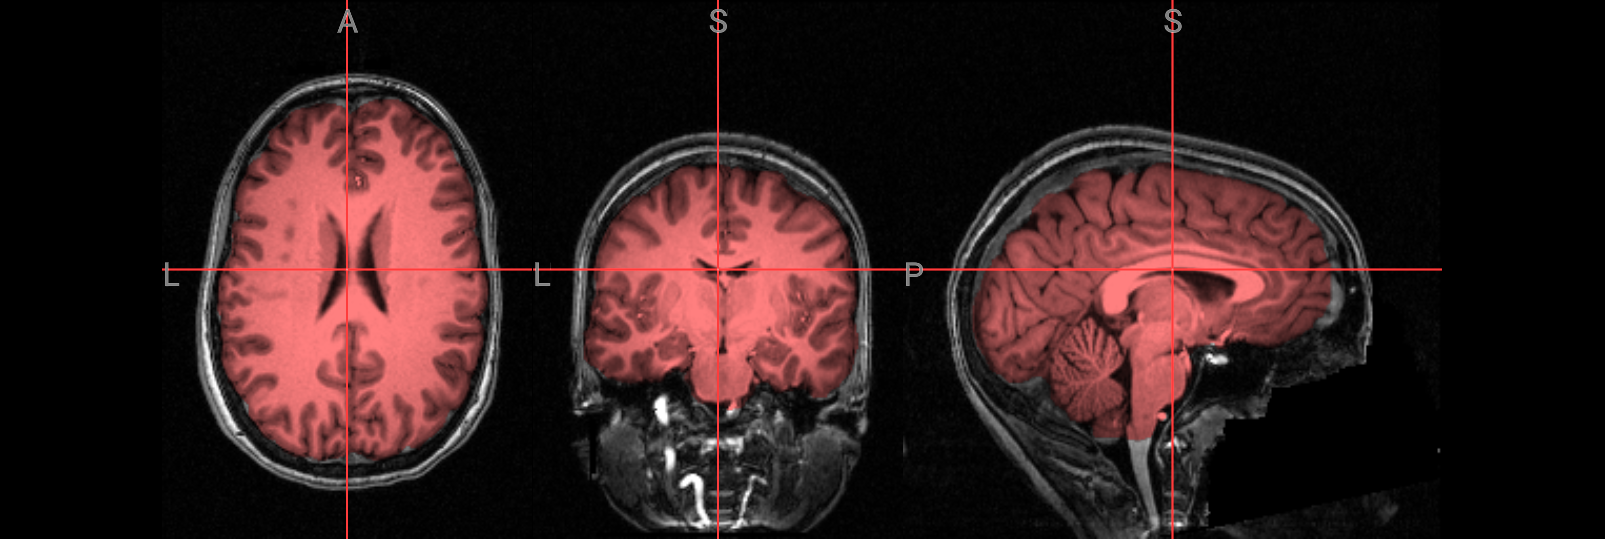

Visualization of the brain extracted image#

Check the following overlay image for areas where too much brain tissue has been removed or where parts of the skull haven’t been fully stripped away. The goal is to produce an image where the skull and face are completely removed, leaving only the brain—cortex, subcortical structures, brainstem, and cerebellum—intact.

# Visualize the skull-stripped (red) on top of the original T1 anatomical image

nv = NiiVue()

nv.load_volumes([

{"path": "./ds000102/sub-08/anat/sub-08_T1w.nii.gz", "name": "T1w", "colormap": "gray"},

{"path": "./FSL_preproc/sub-08_T1w_brain.nii.gz", "name": "T1w_brain", "colormap": "red", "opacity": 0.5}

])

nv

Image(url='https://raw.githubusercontent.com/NeuroDesk/example-notebooks/refs/heads/main/books/images/fsl_preproc_bet_05.png')